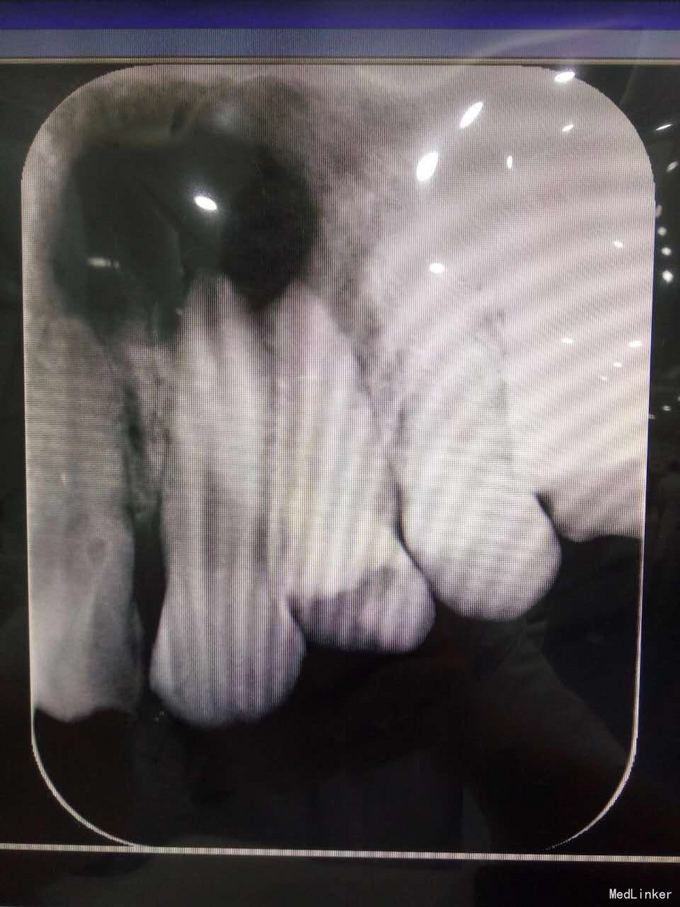

24牙合面龋坏,龋坏较深,未穿髓,龈红,无窦道,无松动 23牙牙体完整无明显松动 22牙牙体完整,腭侧有窦道,无明显松动 X线示23牙根尖牙周组织可见1cmX10cm囊肿,波及22牙及24牙

22牙牙髓部分坏死 23根尖囊肿 24牙髓坏死 1.22牙23牙24牙RCT 2.转外科行23牙囊肿摘除术 23牙MTA根尖封闭,拍片,确定根尖封闭良好,使用热牙胶垂直加压充填,流动树脂垫底,Z350树脂充填抛光 22牙24牙根充,流动树脂垫底,Z350充填抛光